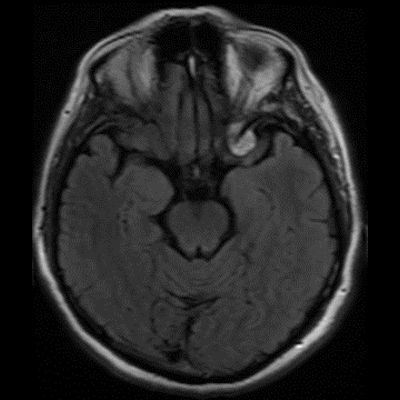

60 yaş, K

Baş ağrısı

Tanınız nedir?